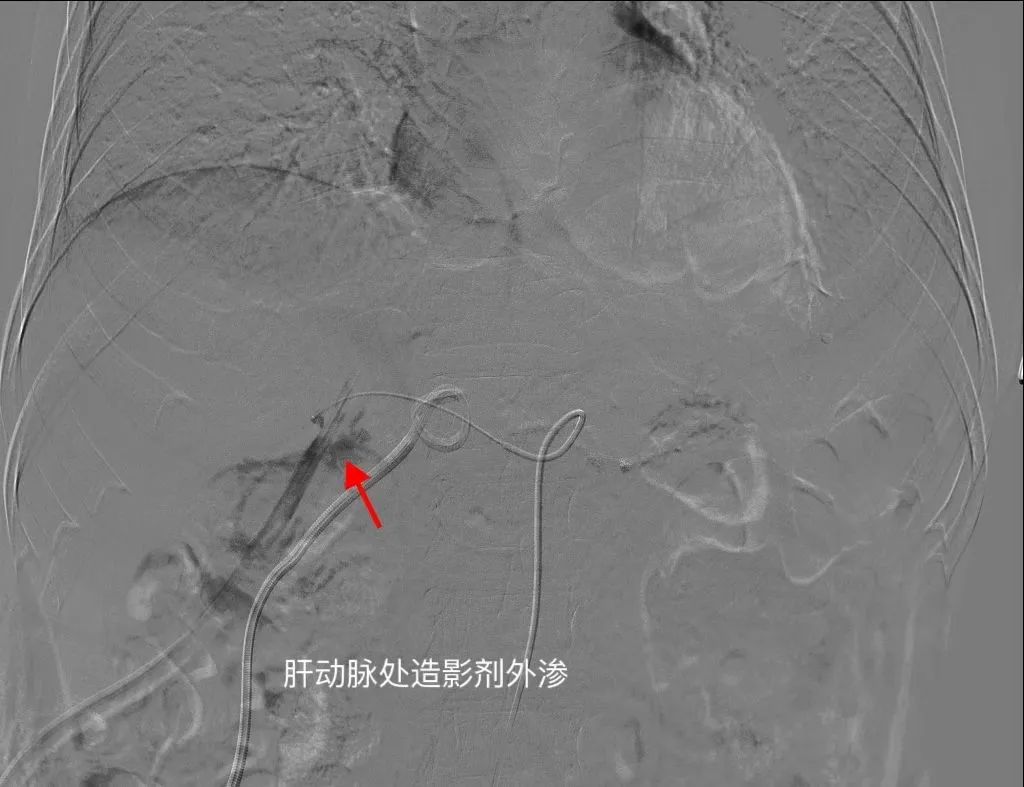

介入造影精准找到出血动脉

术中通过微导管造影,精准找到刘大爷出血点位于肝动脉,进行精准动脉栓塞止血后,顺利完成微创介入手术。手术过程中,刘大爷体征平稳,术后安全返回病房。